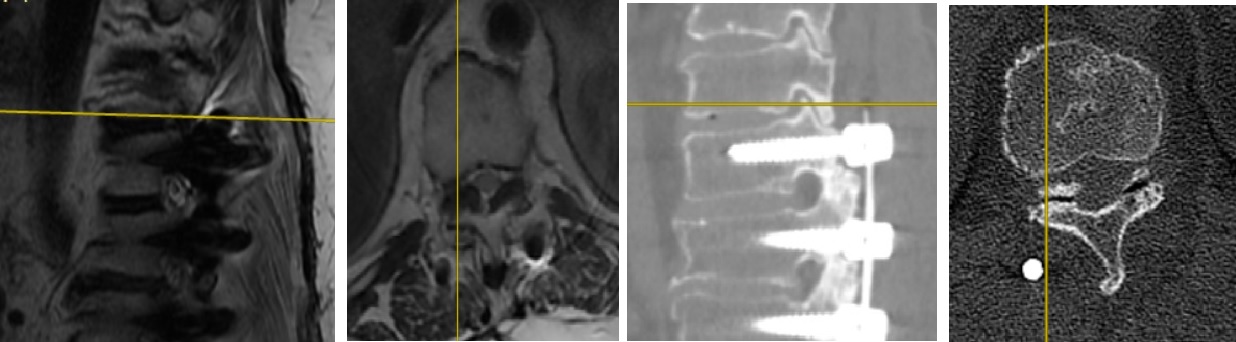

T10-T11 seviyesi

T10-T11 Sağ Taraf Değerlendirmesi T10-T11 Sol Taraf Değerlendirmesi

Resim 4: MRG ve BT incelemeleri bir araya getirildiğinde enstruman sisteminin kranial ucunda (T10-T11 seviyesi) hızlanmış komşu segment dejenerasyonu görülmekte. Ligamentum flavum kalınlaşmasına bağlı olarak spinal kanal ılımlı derecede daralmış, artmış hareket genliği nedeniyle dejenere olan intervertebral disk ve faset eklemler içinde gaz gölgeleri oluşmuştur. Azalmış lomber lordoz nedeniyle sagittal planda dengeyi koruyabilmek için torasik kifoz düzleşerek torasik veretebraları retrolistezise zorlamış ve bunun sonucunda superior artiküler çıkıntılar intervertebral foramenleri daraltmıştır. Aynı bulgular daha hafif olarak T9-T10 seviyesinde de vardır.

L4-L5 seviyesi

L4-L5 MRG Kesitleri L4-L5 Sağ Taraf L4-L5 Sol Taraf

Resim 5: L4-5 seviyesindeki santral (en üst sıra), sağ foraminal (orta sıra) ve sol foraminal (alt sıra) görüntülerde iki yanlı olarak kanal içinde lateral reseslerin, solda daha belirgin olarak iki yanlı L4-5 foramenlerinin daraldığı görülmekte.

L5-S1 seviyesi

L5-S1 MRG Değerlendirmesi

Resim 6: L5-S1 seviyesi nisbeten daha iyi korunmuştur ve lateral resesler açıktır. Ancak solda gevşeyen L5 vidasının L5 pedikülünün alt duvarını erode ederek forameni daralttığı görülmekte (L4-5 resimleri alt sıra). L5-S1 sağ nöral foramen normaldir (L4-5 resimleri orta sıra).

Sonuç olarak hastada üst uçta (T10-T11) komşu segment dejenerasyonu, alt uçta L4 ve L5 vidalarında gevşeme, L4-5 seviyesinde iki yanlı lateral reses ve foramen stenozu, L5-S1 seviyesinde solda gevşeyen L5 vidasına bağlı olarak foramen stenozu saptandı.